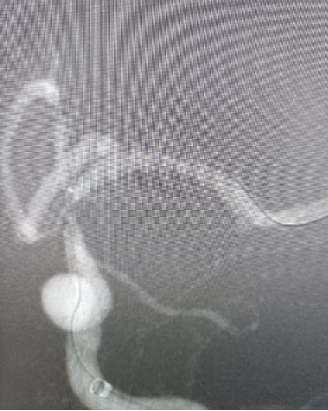

赛诺神畅 NOVA DES®内药物洗脱支架2.5*12mm到位。

释放后造影。

导丝怎么扩【载药时代 球扩天下】NOVA DES®颅内药物洗脱支架在颈内动脉颅内段重度狭窄的应用两例!滕州市中心医院&山西医科大学第二医院_https://www.jmylbn.com_新闻资讯_第20张

植入后造

导丝怎么扩【载药时代 球扩天下】NOVA DES®颅内药物洗脱支架在颈内动脉颅内段重度狭窄的应用两例!滕州市中心医院&山西医科大学第二医院_https://www.jmylbn.com_新闻资讯_第21张

图像放大。

导丝怎么扩【载药时代 球扩天下】NOVA DES®颅内药物洗脱支架在颈内动脉颅内段重度狭窄的应用两例!滕州市中心医院&山西医科大学第二医院_https://www.jmylbn.com_新闻资讯_第22张